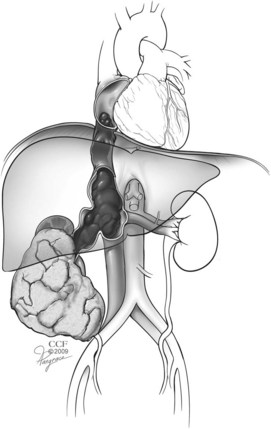

One of the unique features of RCC is its frequent pattern of growth intraluminally into the renal venous circulation, also known as venous tumor thrombus. In extreme cases this growth may extend into the IVC with cephalad migration as far as the right atrium or beyond (Fig. 49–25). The absence of metastases in many patients with vena caval extension is an intriguing aspect of this cancer’s behavior (Gettman and Blute, 2002; Wotkowicz et al, 2008). Forty-five to 70 percent of patients with RCC and IVC thrombus can be cured with an aggressive surgical approach including radical nephrectomy and IVC thrombectomy (see Key Points box). In general, patients with tumor that is otherwise confined to the kidney and nonadherent thrombi have the best prognosis; those with tumor extending into the perinephric fat, lymph node involvement, or direct invasion of the wall of the IVC are at much higher risk for recurrence (Hatcher et al, 1991; Montie et al, 1991; Glazer and Novick, 1996; Gettman et al, 1999; Naitoh et al, 1999; Sweeney et al, 2002b; Bissada et al, 2003; Kim et al, 2004a; Moinzadeh and Libertino, 2004; Leibovich et al, 2005b; Haferkamp et al, 2007; Zini et al, 2008).

Figure 49–25 Schematic illustrating renal cell carcinoma in the right kidney with tumor thrombus extending through renal vein into the inferior vena cava and terminating in the right atrium.

(Reprinted with permission, Cleveland Clinic Center for Medical Art & Photography © 2007-2009. All Rights Reserved.)